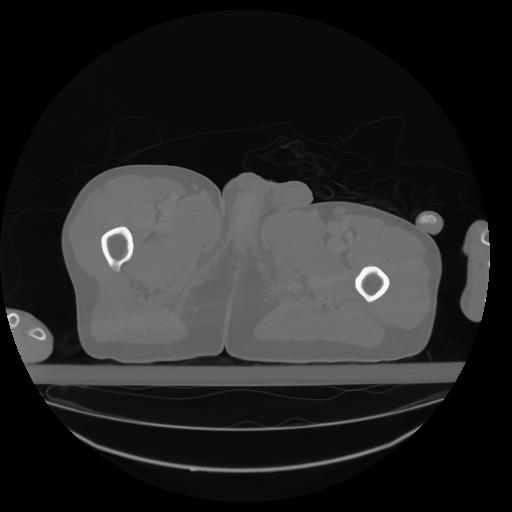

27 CUERPO,CE,Axial,3.0,CUERPO,,